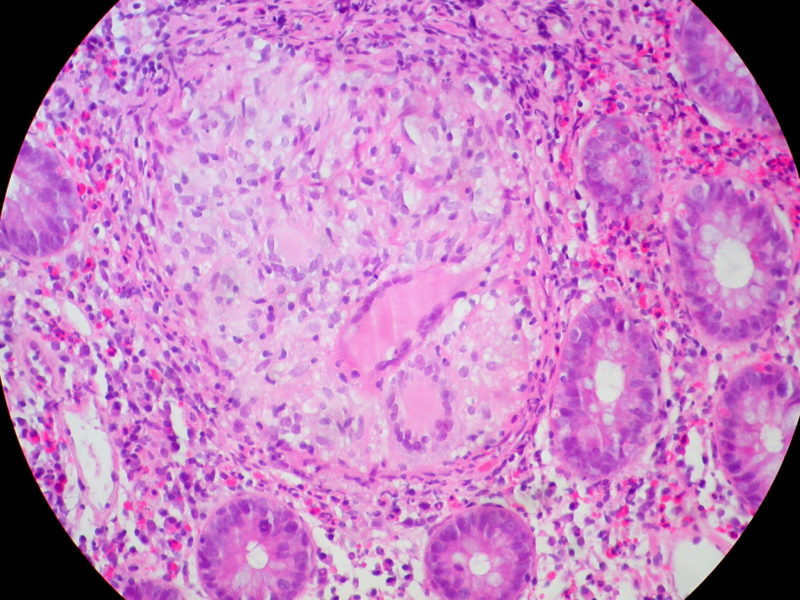

Ulcerative colitis is an inflammatory bowl condition. It causes soreness along the large intestines and rectum lining. Sometimes ulcerative colitis [...]

U lcerative colitis is an inflammatory bowl condition. It causes soreness along the large intestines and rectum lining. Sometimes ulcerative colitis causes bloating, diarrhea and pain. It can be caused by some foods that cause irritation whenever one eats, as such colitis diet menu should be observed.